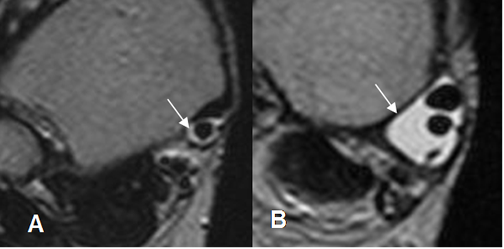

Fig 88. Tenosinovitis del tibial posterior.

A: RM axial en T2. Escaso líquido rodeando el tendón, como hallazgo normal.

B: RM axial en T2. Significativa cantidad de líquido alrededor de los tendones del tibial posterior y flexor largo de los dedos, por tenosinovitis.